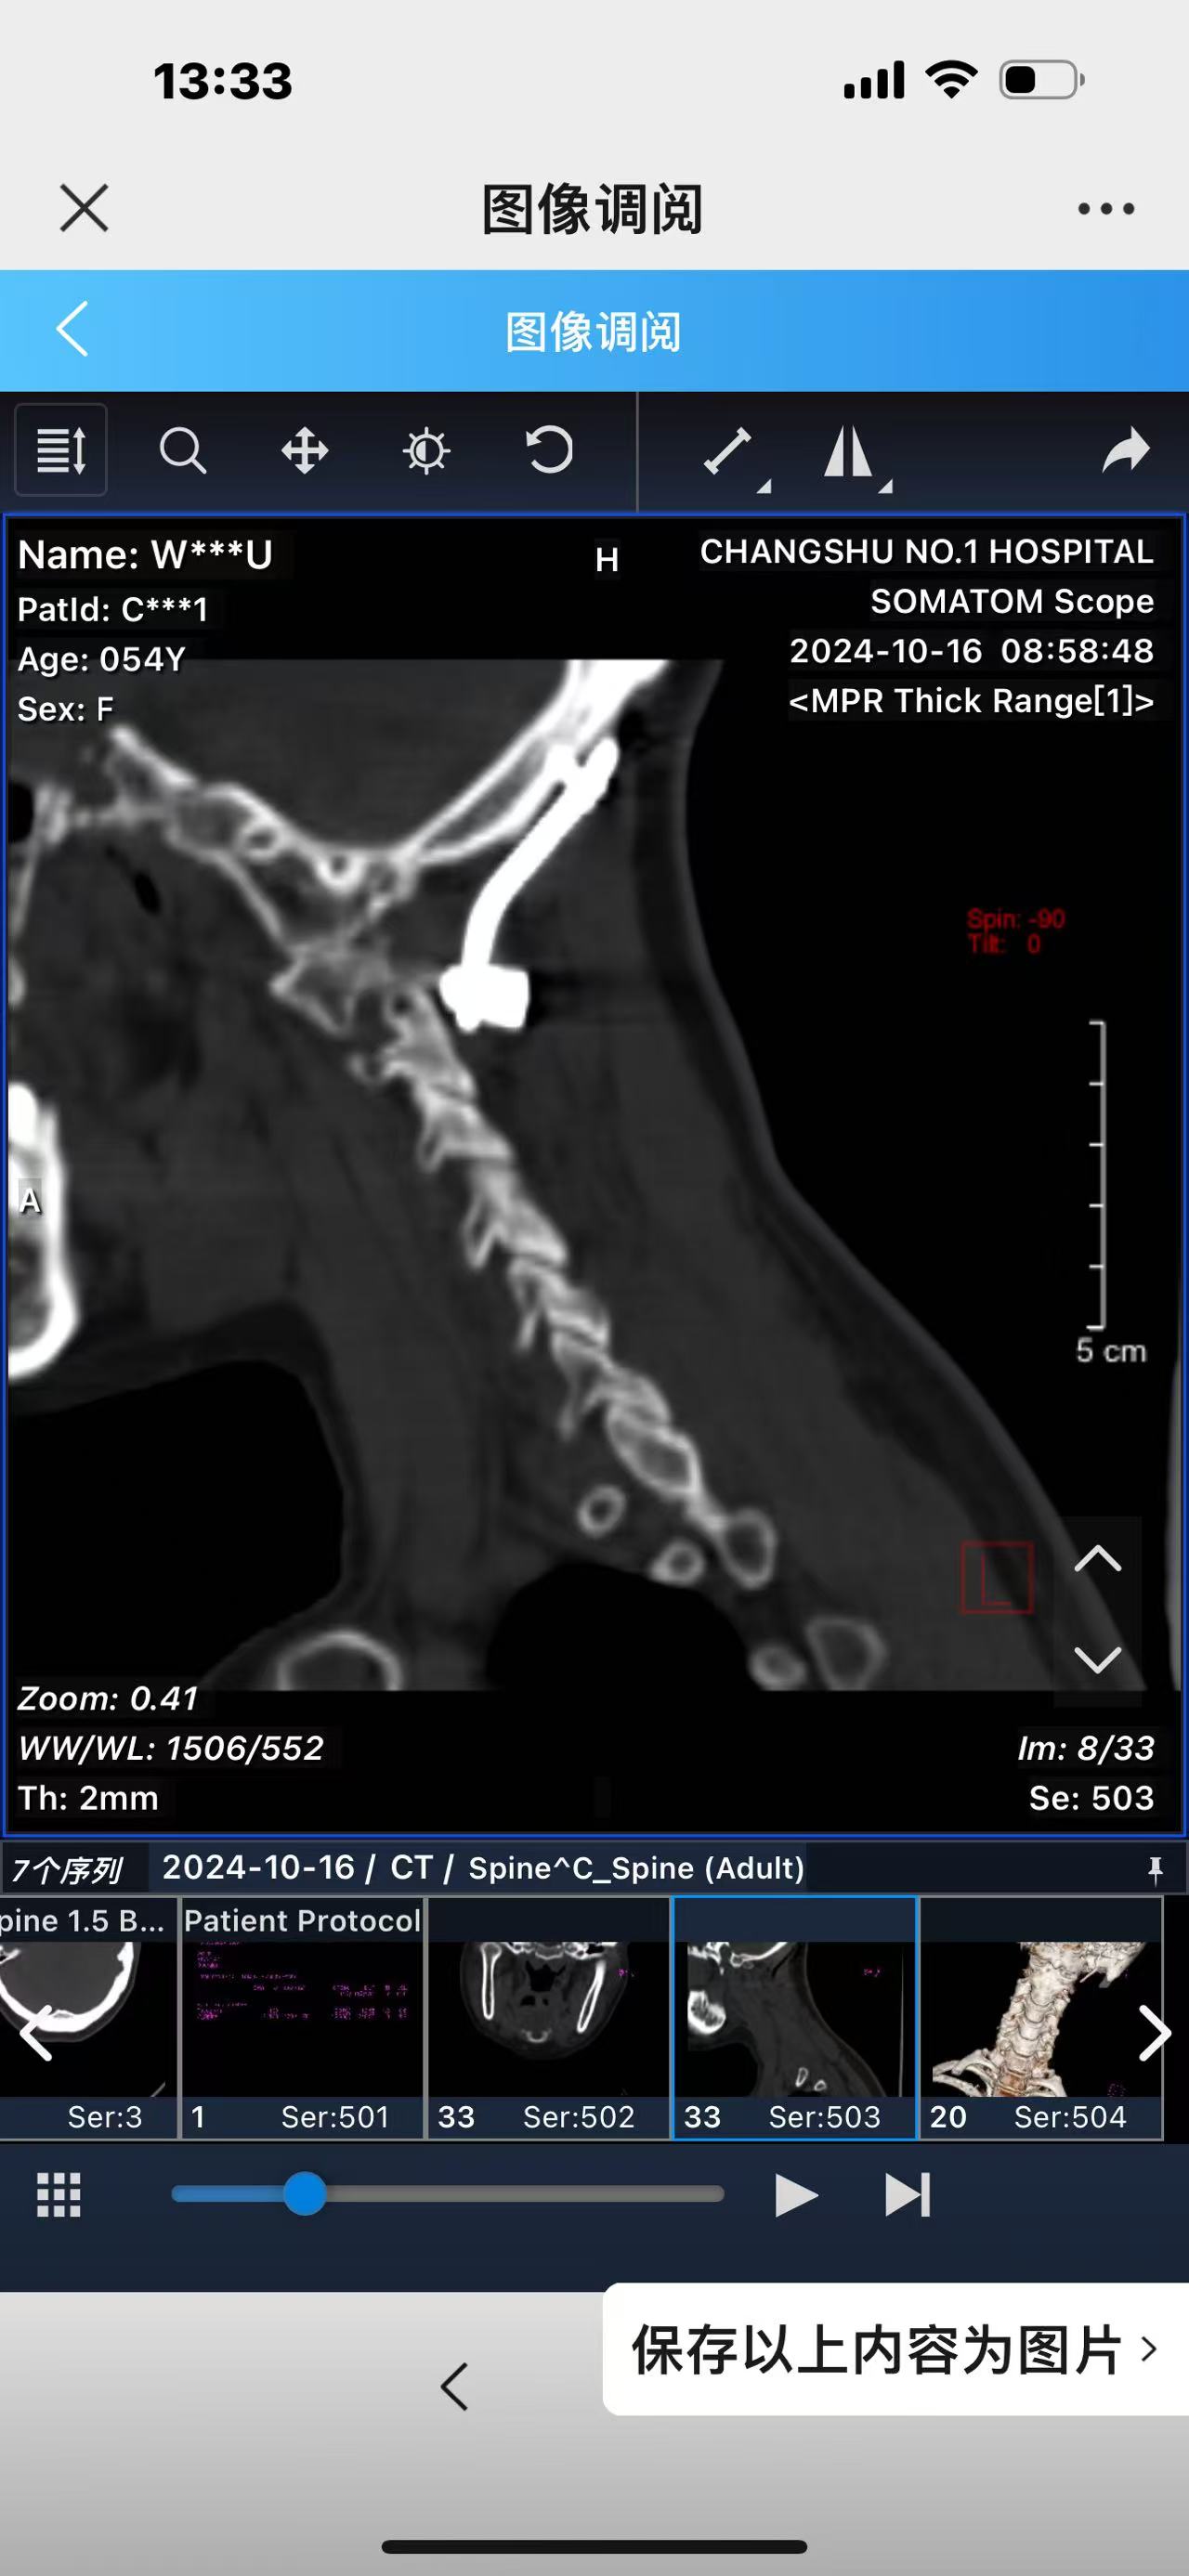

• 诊断:寰枢椎脱位,颅底凹陷

• 影像:

• 术后影像: